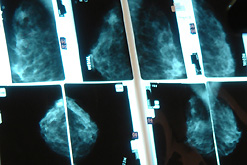

Image: breast check

It has been announced at the Fourth European Breast Cancer Conference that Faslodex, the first of a new kinder class of breast cancer drug, is to be launched in Britain this summer.